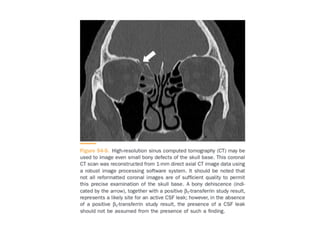

• HRCT and MRI Cisternography

• HRCT:

• Thin-section axial and coronal scans of cranial and facial

region, including all the paranasal sinuses and petrous

temporal bones.

• Demonstrate fractures and bone defects well than MRI.

• Also show protruding soft-tissue (meningoencephalocele )

through the bony defect , and demonstrate focal fluid

accumulation in the sinuses (ethmoid, frontal, sphenoid,

and maxillary sinuses), and pneumocephalus in some

cases.

• CT imaging detects the fluid poorly and may not identify

exact site of leak when there are multiple fractures or

dehiscence